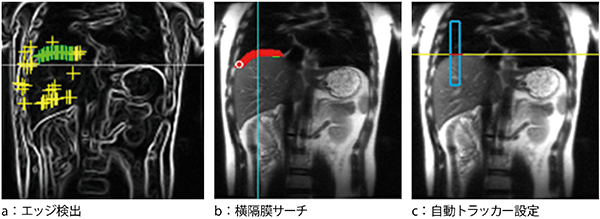

2.機械学習を用いた横隔膜自動検出

“Auto-Navigator Tracker機能”は,位置決め用の画像から患者ごとの横隔膜の位置を自動プロットし,最適な横隔膜トラッカー位置を半自動でセッティングする撮像アシスト機能である(図6)。横隔膜の位置検出には機械学習のアルゴリズムを用いており,患者の体格や状態によらず精度の高いトラッカー設定が可能で,従来よりも体幹部においてスムーズな検査を行うことができる。

図6 機械学習によるワークフローの簡素化(Auto-Navigator Tracker機能)